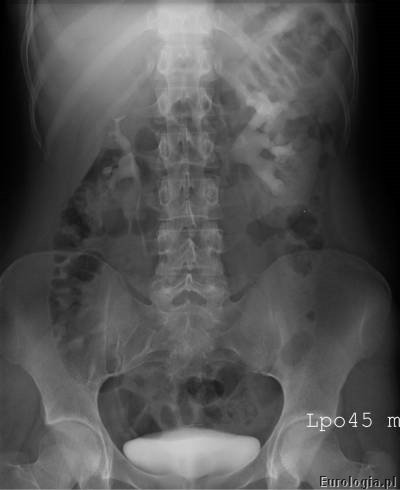

Mocz spływający z układu kielichowo – miedniczkowego moczowodami do pęcherza zakontrastowuje układ moczowy dzięki czemu na zdjęciach rentgenowskich możliwa jest ocena czy spływ jest swobodny, czy utrudniony. W przypadku utrudnionego spływu badanie z reguły pozwala na ocenę miejsca i rodzaju przeszkody.

Zakontrastowany mocz spływając do pęcherza wypełnia go co umożliwia ocenę jego wnętrza. Guzy pęcherza mogą być widoczne jako ubytki wypełnienia. W czasach kiedy nie było dostępu do ultrasonografii zdjęcie urograficzne wykonane po oddaniu moczu było podstawą do oceny stopnia zalegania moczu po mikcji.

Urografia wykonywana jest w pracowni rentgenowskiej i trwa około 30 minut. W czasie badania pacjent układany jest w pozycji leżącej na plecach na stole rentgenowskim. Pierwsze zdjęcie wykonane przed podaniem kontrastu nazywane jest zdjęciem przeglądowym nerek i pęcherza, na którym możliwe jest uwidocznienie cieni mogących być uwapnionymi złogami w układzie moczowym. Kolejnym etapem badania jest dożylne podanie kontrastu przez wenflon wkłuty na przedramieniu pacjenta. Po podaniu kontrastu wykonywana jest seria zdjęć rentgenowskich w odpowiednich odstępach czasu. Czasami konieczne jest wykonanie tak zwanych późnych zdjęć urograficznych w sytuacji gdy w standardowym czasie nie uzyskano zakontrastowania układu kielichowo – miedniczkowego lub moczowodu.

Przykładowe badanie urograficzne :